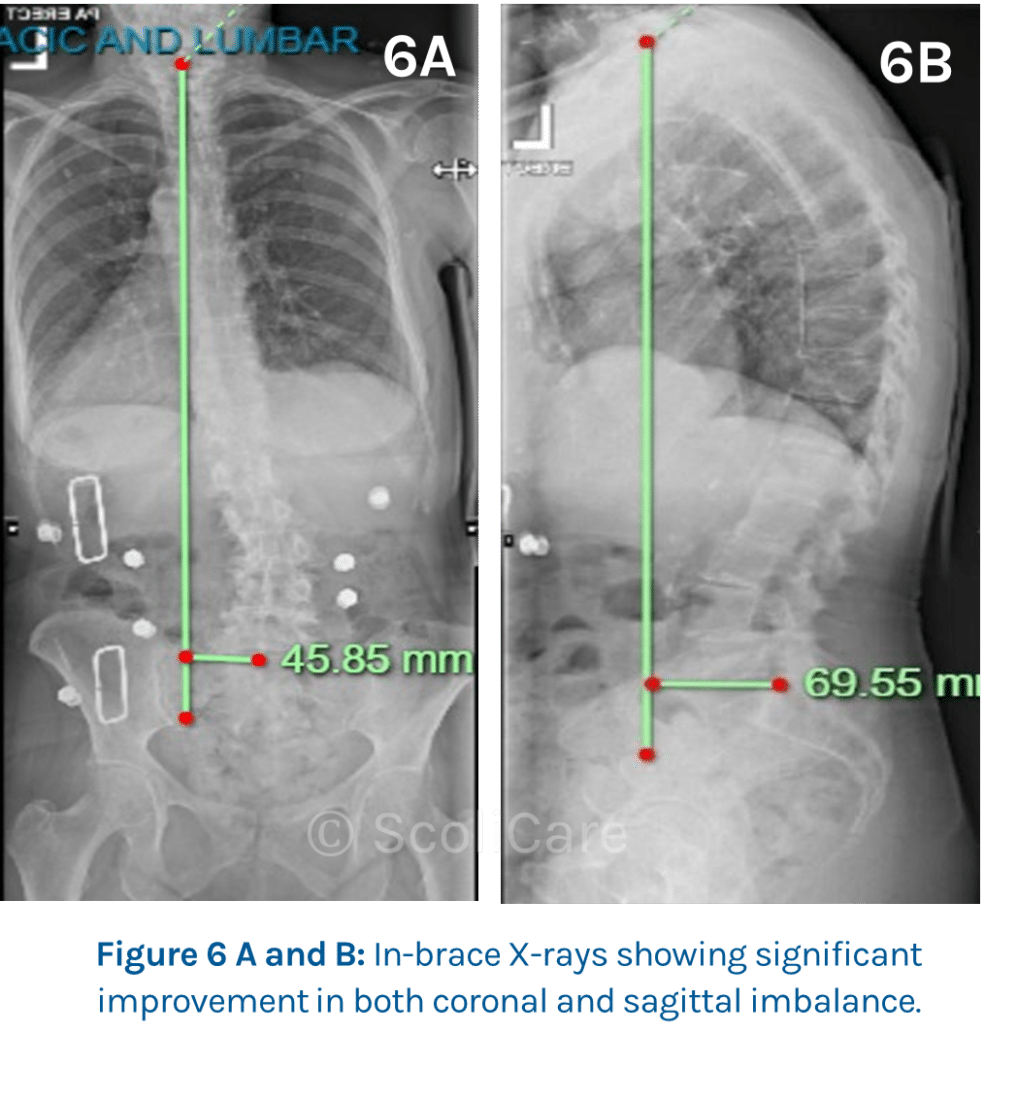

The patient was subsequently prescribed a 3D designed custom scoliosis brace , and the corrective action of the brace can be seen in the PA and lateral X-rays (Figure 6). The recommendation was that the patient wear the brace for a minimum of 6-8 hours per day or more if needed.

After wearing the brace for several hours, a day for a period of 18-months, a significant improvement in her coronal imbalance (left lean) by 21.34mm (32.77%), and anterior sagittal imbalance by 104.12mm (70.97%) can be seen (Figure 7). With the patient’s posture notably improved from the initial consult (Figure 8 and Figure 9) with wearing the brace for up to 8 to 10 hours per day.